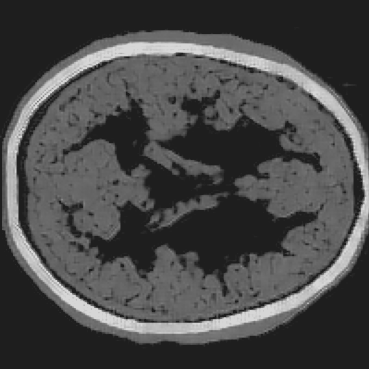

Refer to caption

(b) Full-transducer dataset

Figure 7: Stacked TRA Image with (a) Partial-transducer dataset and (b) Full-transducer dataset

To evaluate performance, we construct two acquisition setups using the same horizontal 2D slice of the phantom: (i) an idealized full-transducer dataset (Figure 3(b)) providing near-uniform coverage along the head contour, and (ii) a partial-transducer dataset (Figure 6) designed to reflect practical acquisition constraints. In the partial setup, a linear array with 51-element is repositioned around the head; for each view, the central element transmits and all other 50 elements receive. The partial setup includes 50 sweeps covering the full 360, meaning that for each sweep, the source and receivers rotate by 360/50=7.2360/50=7.2^{\circ}. Sweeping 50 views yields, per 2D slice, a channel tensor of shape (T,Ns,Nr)=(5001,50,50)(T,N_{s},N_{r})=(5001,50,50). The key distinction between these two datasets is their aperture: full-transducer provides near 360 coverage in a single placement, whereas partial-transducer attains coverage by aggregating neastest 50 receivers in a single placement, which is only around 36. Particularly, the partial-transducer setup includes only 50 sweeps, while the full-transducer setup uses all receivers covering the entire brain, with each transducer acting as a source in turn while the others serve as receivers. Compared to the full-transducer, the partial-transducer achieves coverage by combining a much smaller number of views. For each sweep, we generate the forward wavefield g(𝐱,t|𝐠){{g}}(\mathbf{x},t|\mathbf{g}) and the back-propagated wavefield p~(𝐱,t|𝐠)\tilde{{p}}(\mathbf{x},t|\mathbf{g}) and generate the TRA fragment with Eq. (7) (example in Figure 6). With the physical TRA method, the TRA fragment can be stacked to give the stacked TRA image. To validate the differences between the two datasets, we generated stacked TRA images using both datasets, as shown in Figure 7. As shown in Figure 7(b), the full-transducer dataset provides significantly greater detail in internal structures. Despite higher levels of noise and artifacts caused by the limited number of views, the partial-transducer dataset is still capable of capturing some meaningful tissue structures.